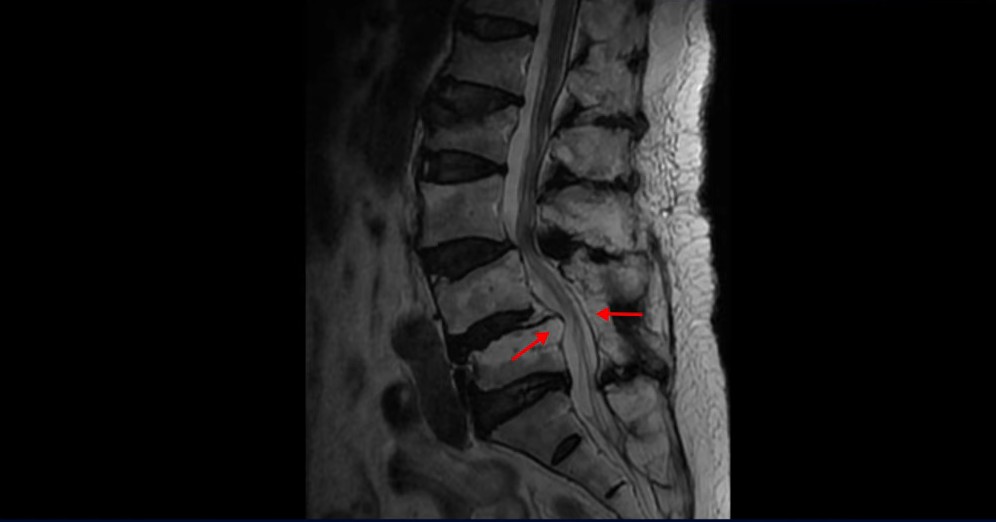

이 환자분은 협착증 수술 예약을 날짜까지 잡아놓고 넘어지면서 압박골절이 발생하고 협착증 증상 즉, 골반과 다리증상이 심하게 악화됩니다. 이분 MRI를 보시면 척추 2번 뼈에는 넘어지면서 생긴 척추압박골절이 보입니다.

4번과 5번 마디는 전방전위증이 있고 15년 전 허리수술을 받은 적이 있어서 척추 후관절과 후궁을 제거한 흔적들이 보입니다.

또 5번 1번에는 왼쪽 신경가지가 빠져나가는 추간공 즉 신경구멍이 많이 좁아져 있습니다. 이 환자분은 허리통증과 함께 왼쪽 다리 증상이 심하셨는데 이것 때문인 것으로 보입니다.